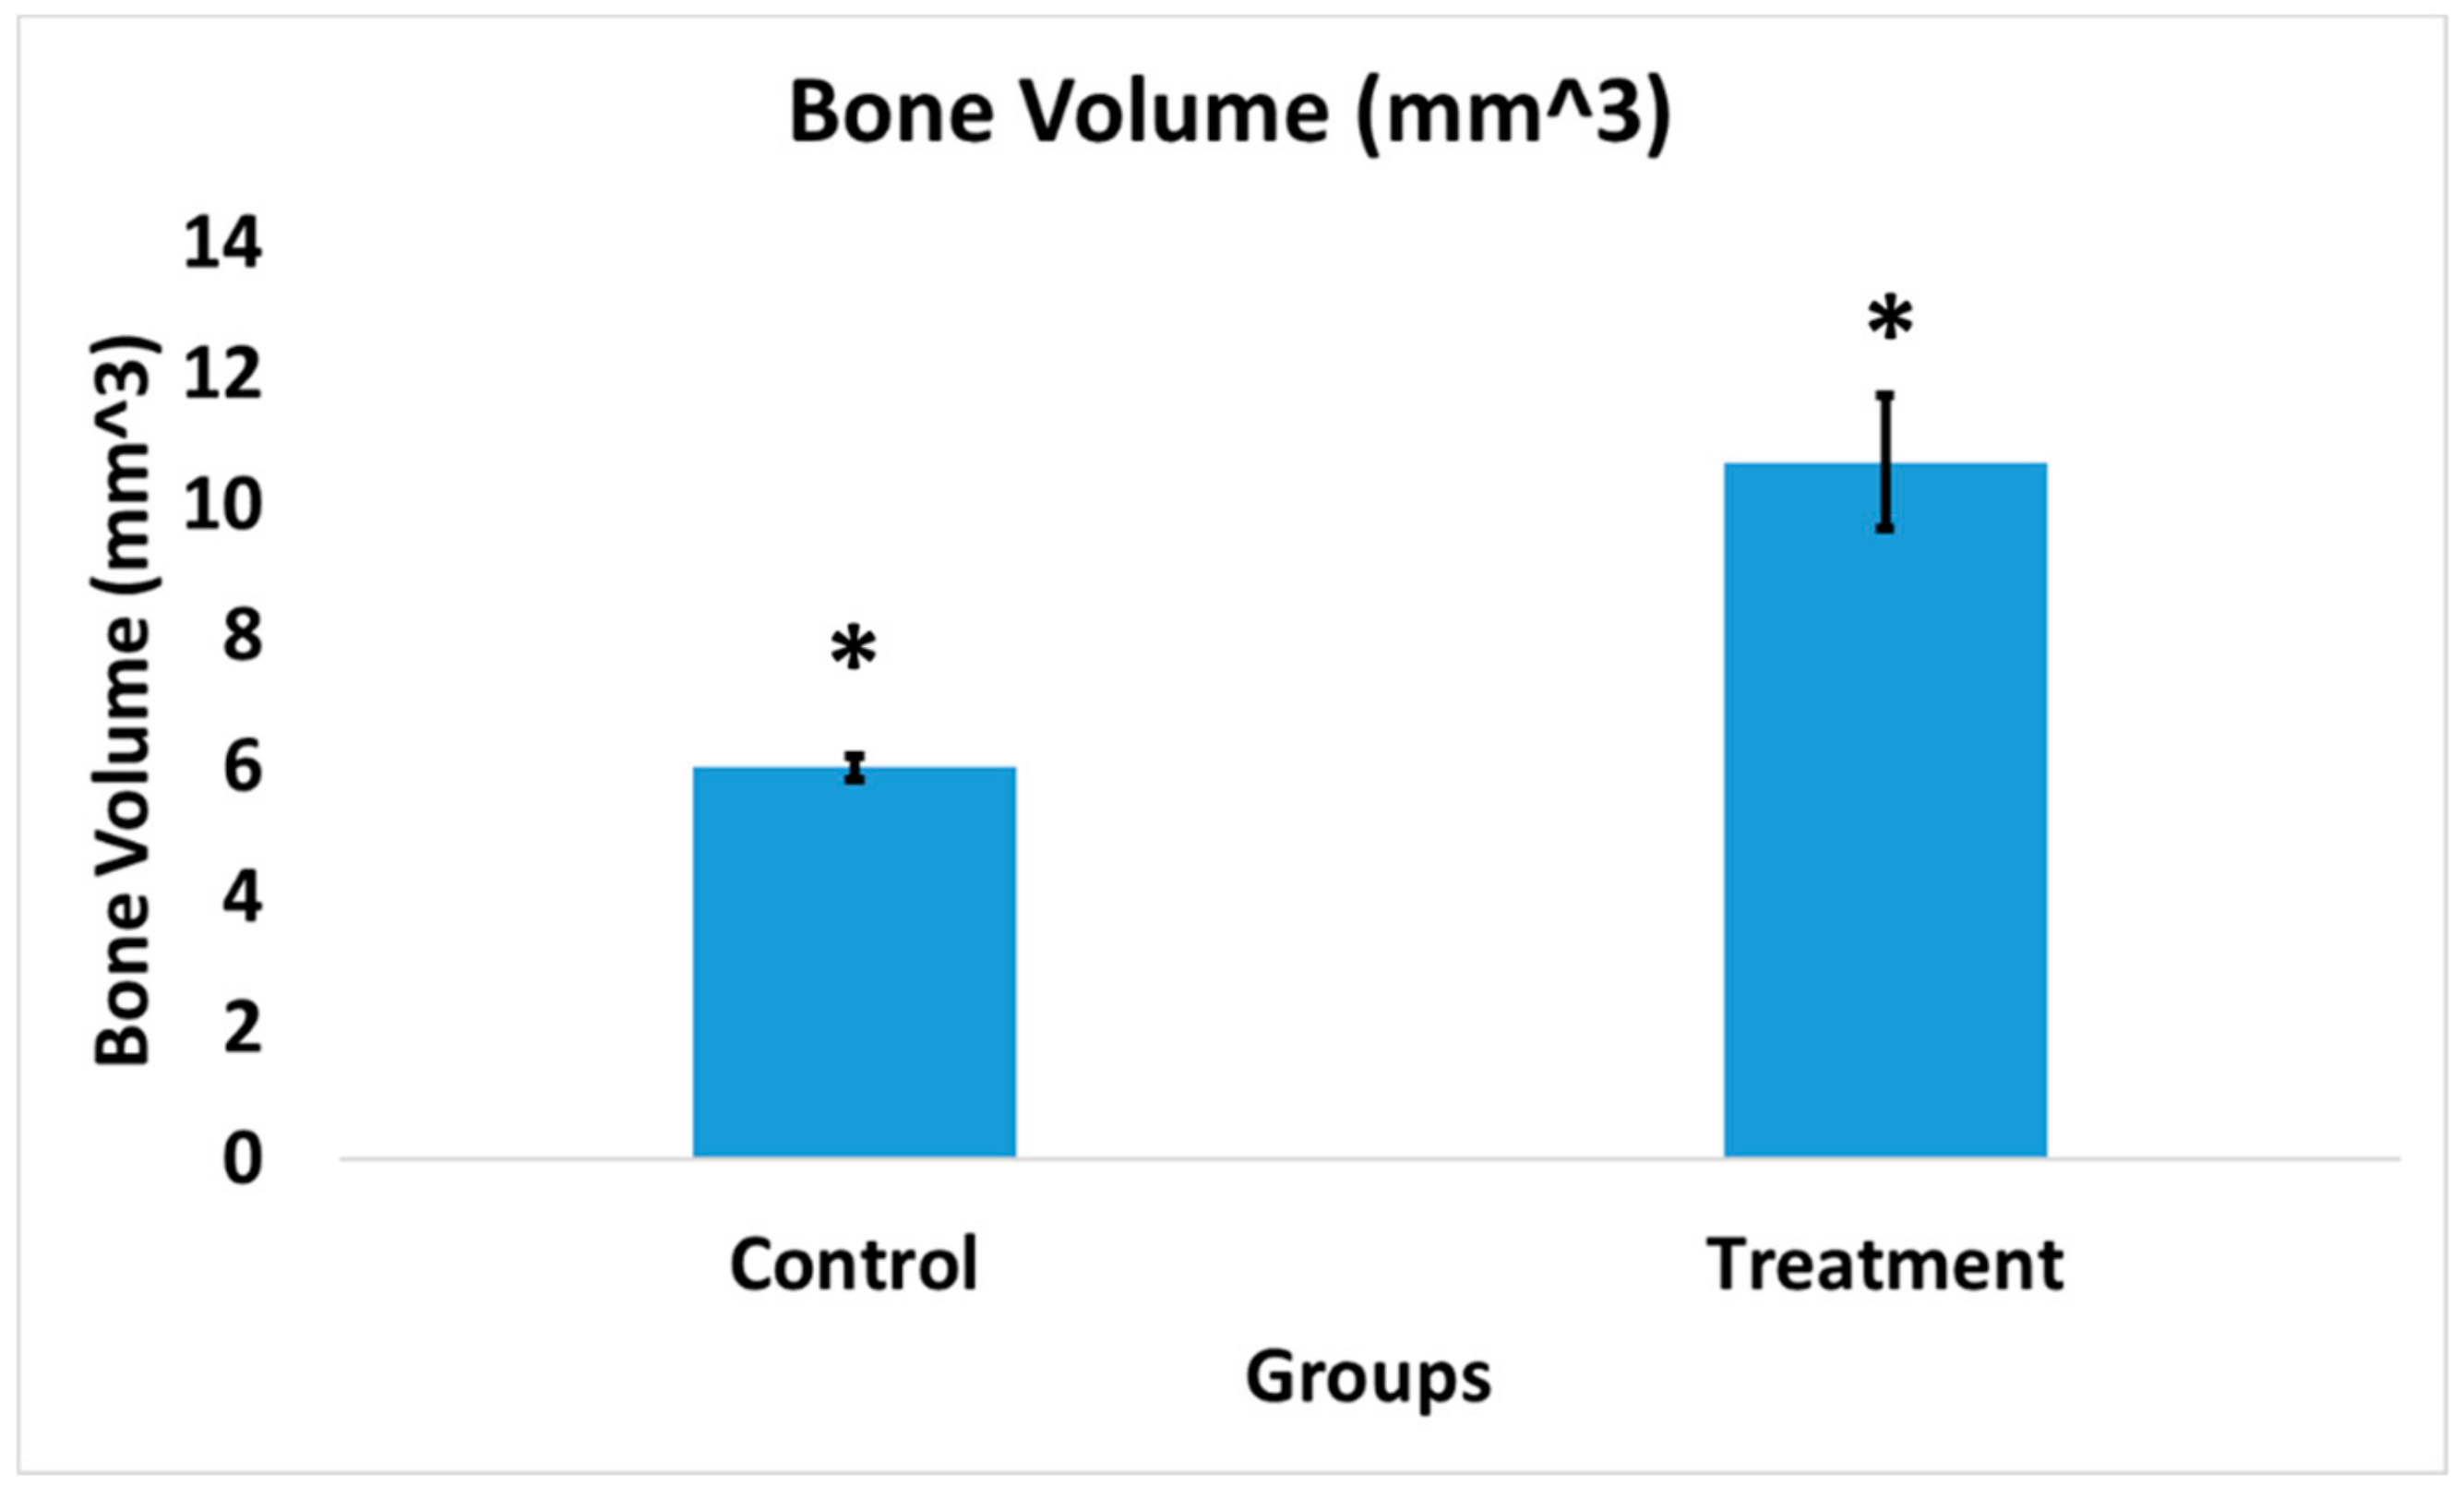

3.9. Bacterial Colony Count

4. Discussion